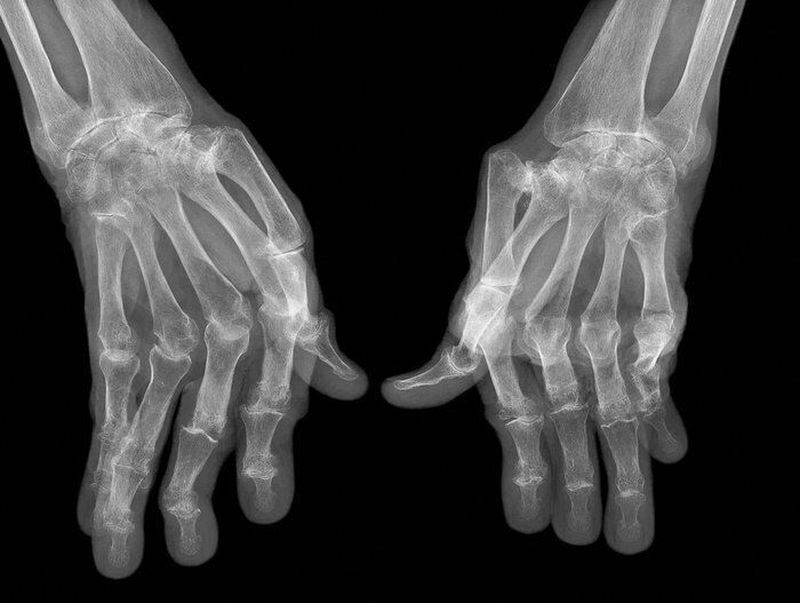

Rheumatoid arthritis